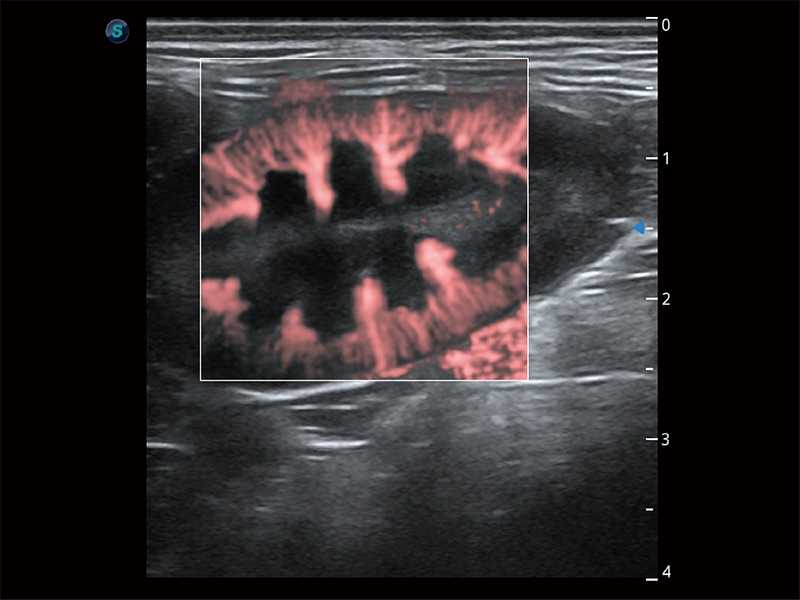

• Micro F 显微血流成像

极大提升超低速微细血流的检出能力,同时更精准地滤除软组织和超声信号,为兽用医生提供以往无法通过常规血流获得的疾病诊断信息。

• Bright Flow 立体血流成像

在传统二维血流成像的基础上,呈现血流的立体感,具有动感的生命力之美。即便是微小的血管也能轻松应对,提高了血流的视觉敏感性。

(犬)肝脏

(猫)胆囊

(犬)肠道

(犬)肾脏显微血流